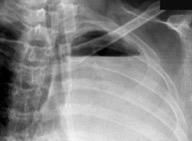

De los pacientes con Tumor de Pancoast

1,7% tienen una radiografía de tórax normal

Fletcher F et al. The normal chest radiograph in bronchial carcinoma. Br Med J. 1976